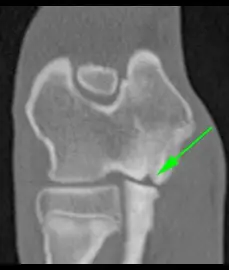

FMCP